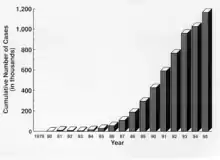

1982: The AIDS crisis

In 1982, the first news of AIDS reached Switzerland. The first names given to it were "gay cancer", "gay disease", and "gay-related immune deficiency" (GRID). No-one knew at the time what caused AIDS, or how the infection spread. The advent of AIDS changed the movement of the mid-eighties completely. Many of the founders died, and LGBT people were stigmatised, leading to CSDs and gay rights demonstrations becoming sporadic rather than annual.

In 1985, ‘’Loge 70’’, all ‘’HA’’ groups, ‘’SOH’’, and the Federal Health Office (BAG) founded ‘’Aids-Hilfe Schweiz’’ (AHS) (AIDS-Help Switzerland). In 1986, the AHS published an AIDS information brochure, which was distributed to all households in Switzerland. The AHS prevention campaign is the most successful prevention campaign in Switzerland.